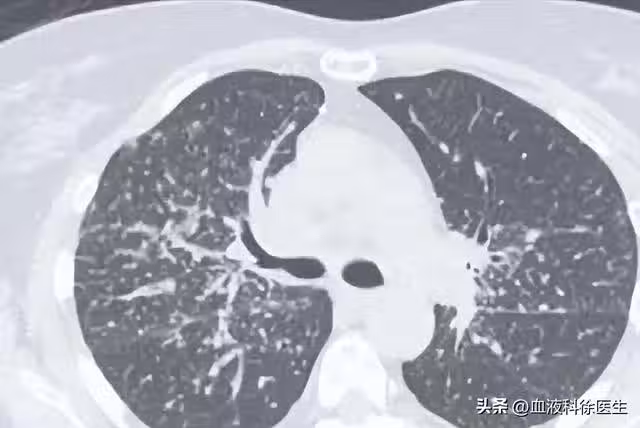

55歲男子5月體檢發現肺結節,年底就肺癌晚期,醫生:警惕肺結節

這便可以解釋為什麼王叔叔身邊的許多同事也被發現有肺結節,因為肺結節的發病率在人群中確實不低,預計隨著吸菸、空氣污染及人口老齡化的影響,檢出率會進一步升高。

既然肺結節的檢出率這麼高,那麼究竟是什麼原因導致了早期肺癌或是肺結節的發生呢?